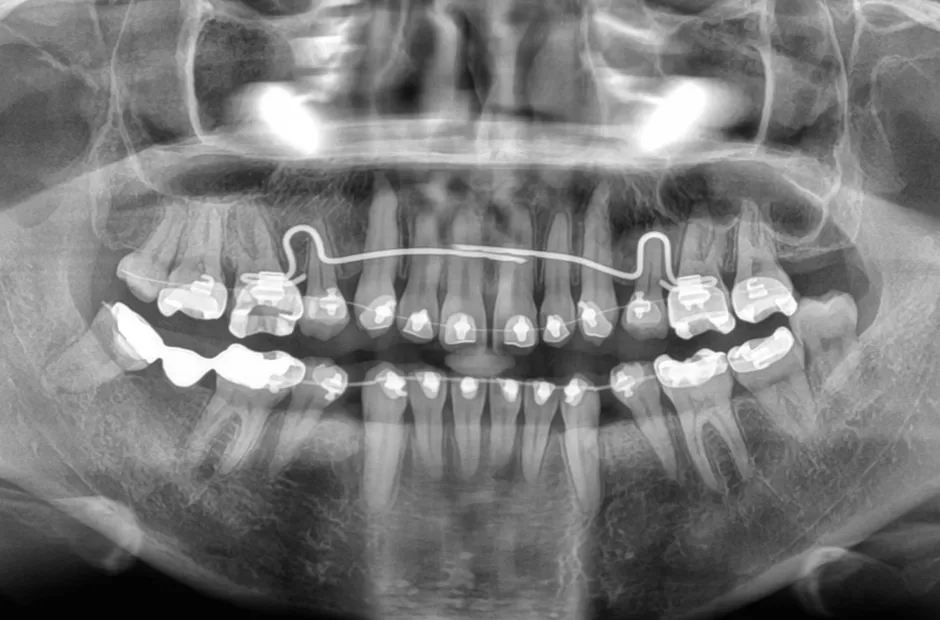

過剰歯

| 診断名・主訴 | でこぼこ |

|---|---|

| 年齢・性別 | 22歳・女性 |

| 治療期間・回数 | 1年6か月 |

| 治療に用いた主な装置 | リンガルブラケット |

| 抜歯部位 | 過剰歯 |

| 治療費 | 100万円(税抜) |

| リスク・副作用 | 装置による違和感・疼痛・歯肉退縮・歯根吸収・虫歯のリスクなど |

治療前

治療中

治療後